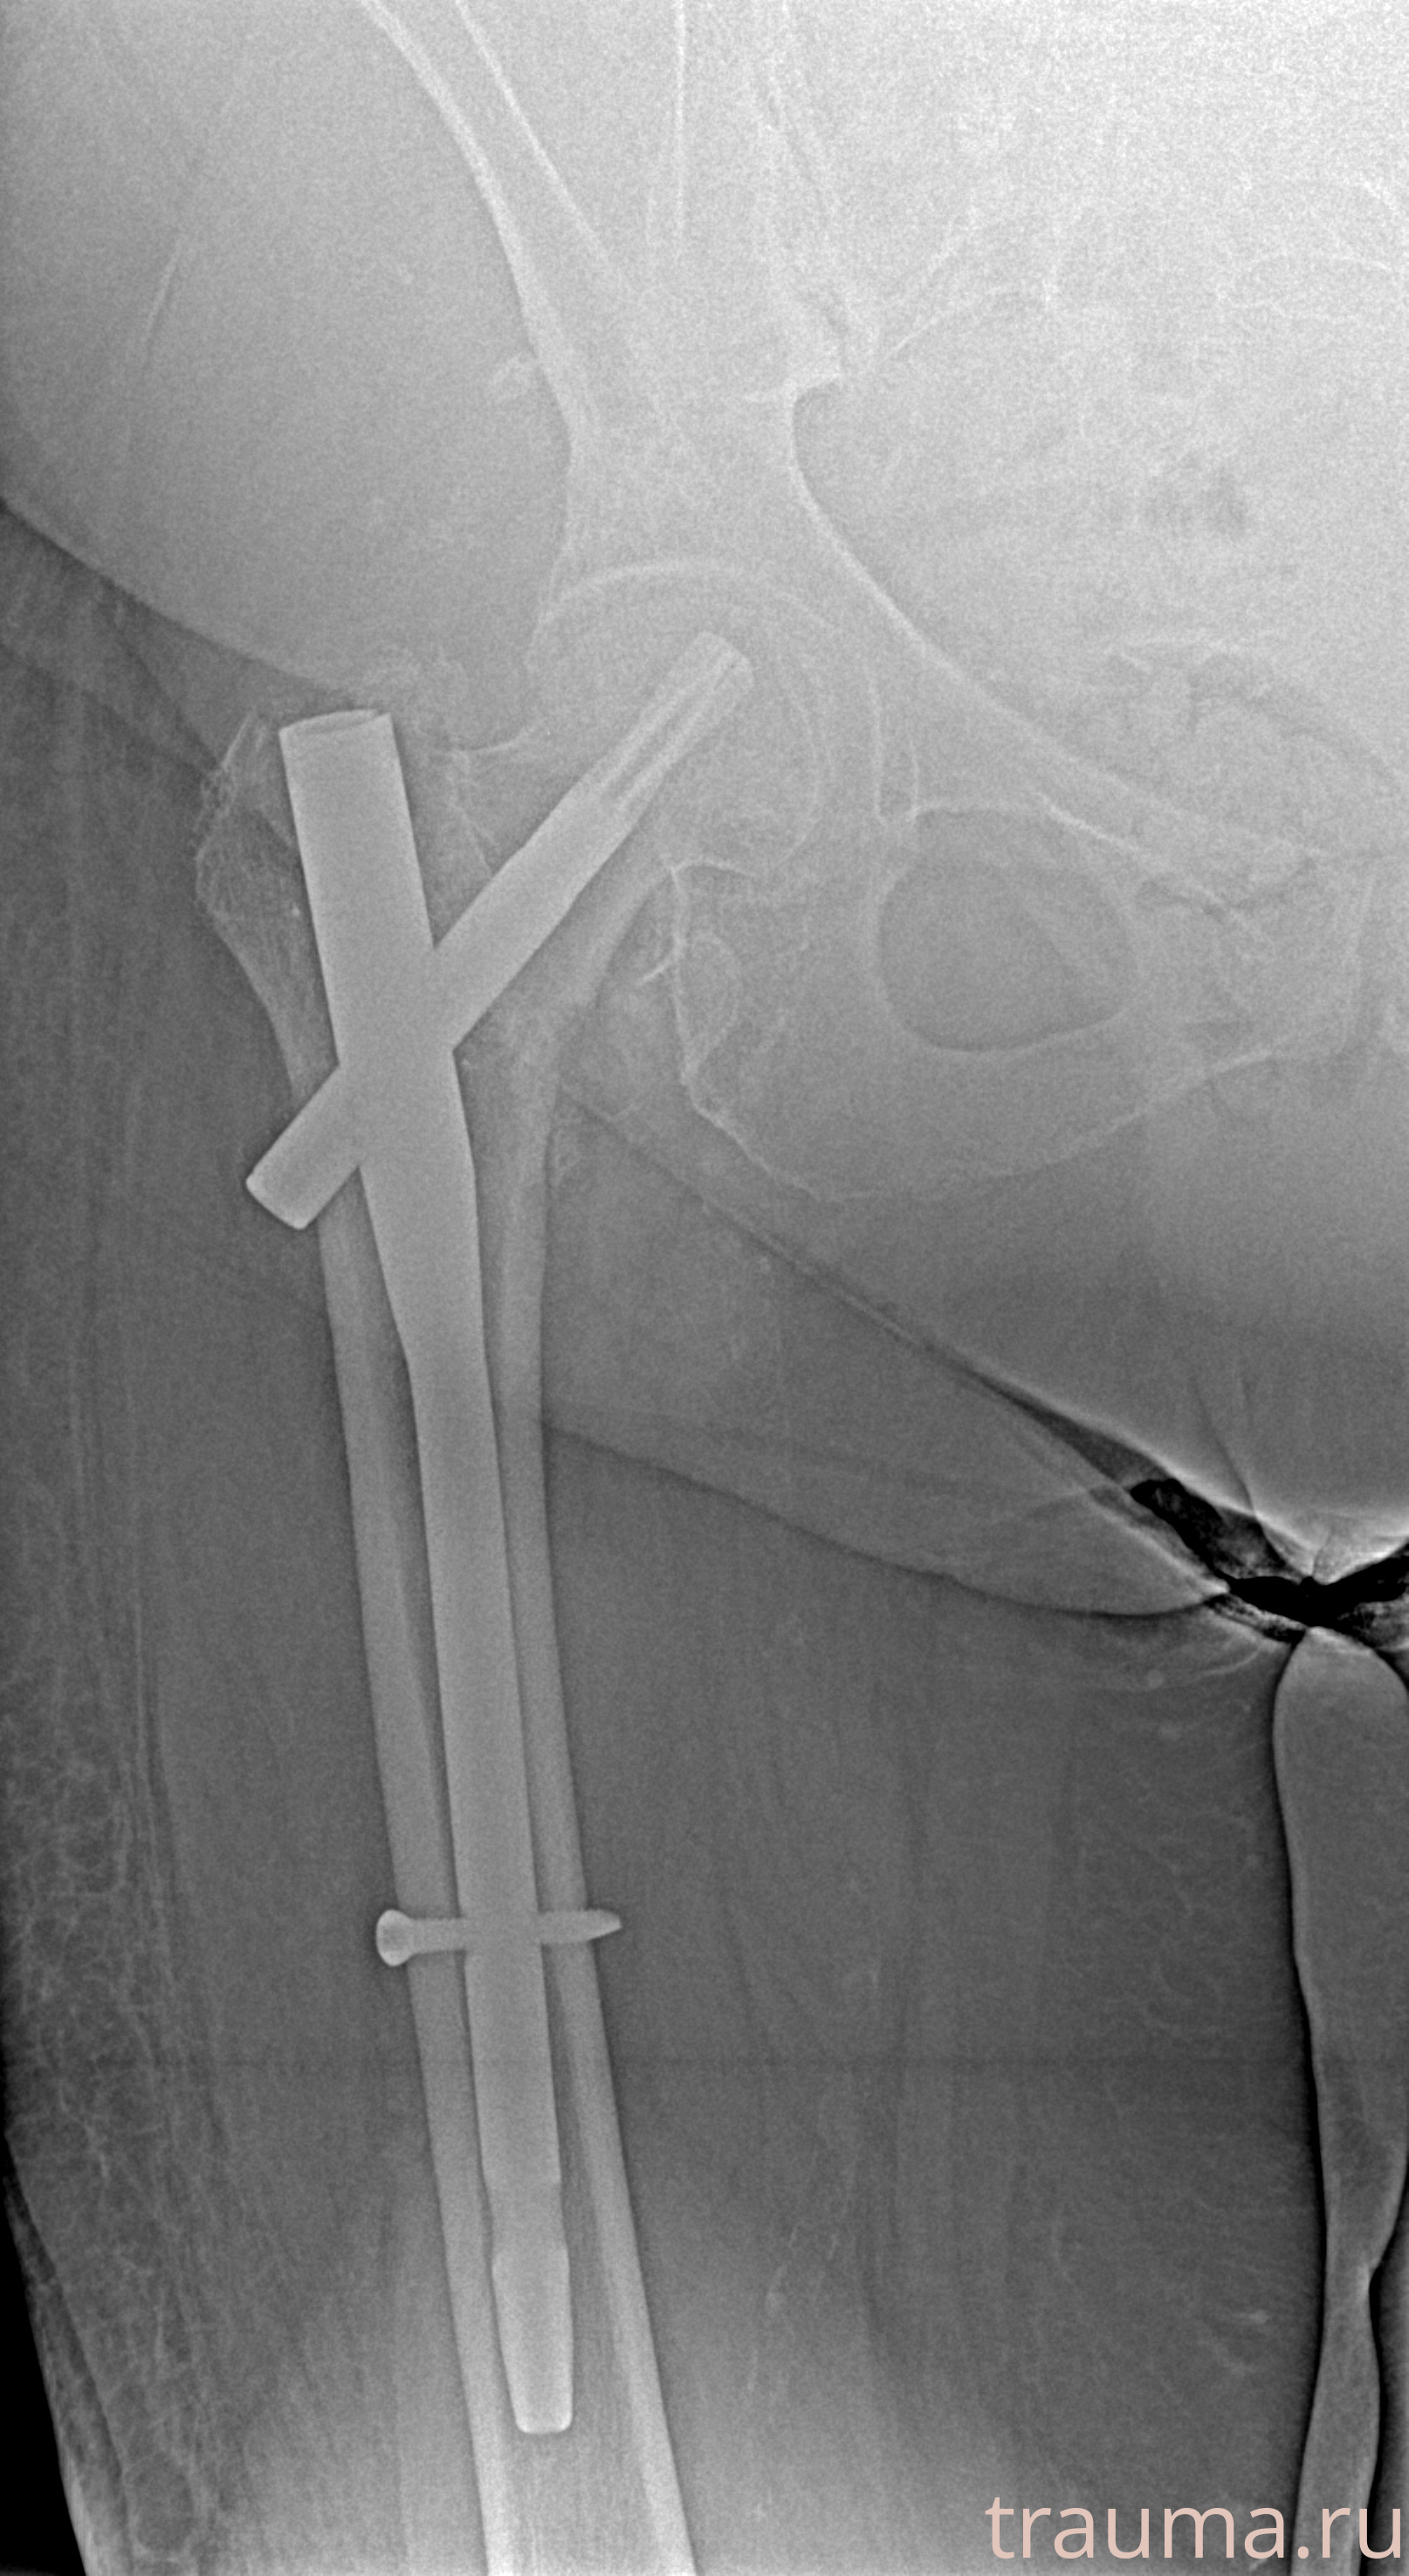

Рентгенограммы